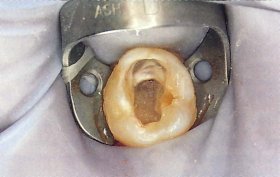

Pulpectomy(乳牙根管治療)

小朋友蛀牙太深故須作根管治療,之後做不鏽鋼乳牙套予以復形.